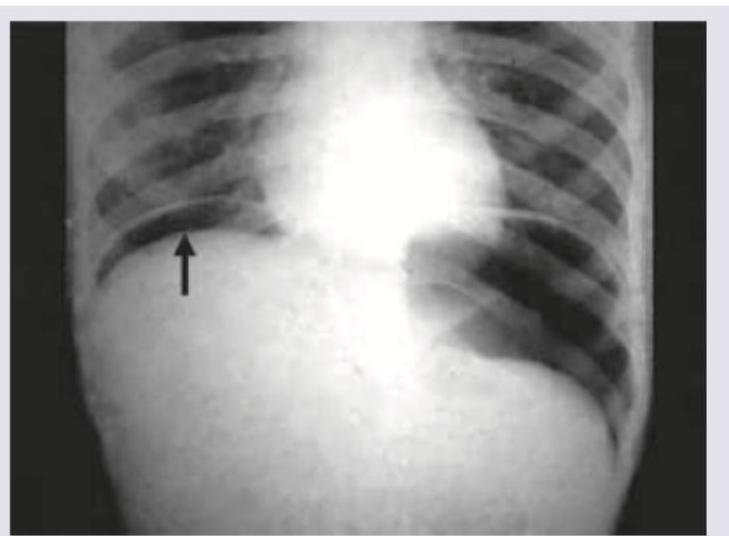

A 30-year-old patient presents with abdominal pain, fever, nausea, vomiting and respiratory distress. On admission BP=80/40 mm Hg and pulse rate is 120 BPM. The following CXR was performed. What is the immediate management? (AIIMS May 2016)